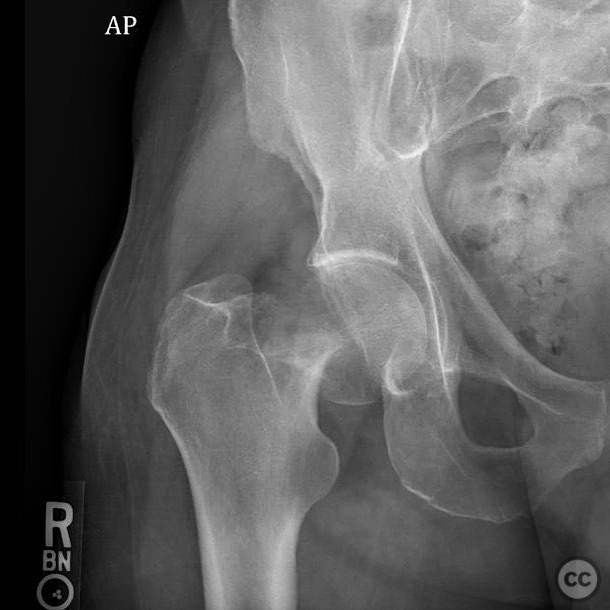

Pipkin IV Femoral Head Fracture with Ace...

Seattle, United States

Femur - AO/OTA 3x

Pipkin IV Femoral Head Fracture Dislocat...

Pipkin IV Femoral Head Fracture with Fem...

Pipkin 2 + cranial peripheral acetabular...